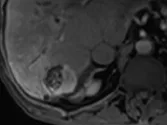

Figure 7. Carcinome hépatocellulaire traité par sorafénib.

Sur l’examen initial (A), la lésion présente deux compartiments sur cette image d’IRM au temps artériel l’un nécrotique, l’autre qui se rehausse, appelé tumeur « viable ».

B. Mesure selon mRECIST du plus grand diamètre de la lésion viable.

C et D. Après quatre mois de chimiothérapie, le compartiment viable de la tumeur passe de 37 à 24 mm, soit une diminution de 35 %. Il s’agit donc d’une réponse partielle, alors que le volume total de la lésion n’a pas changé.

Selon RECIST 1,1, la réponse aurait été « SD »